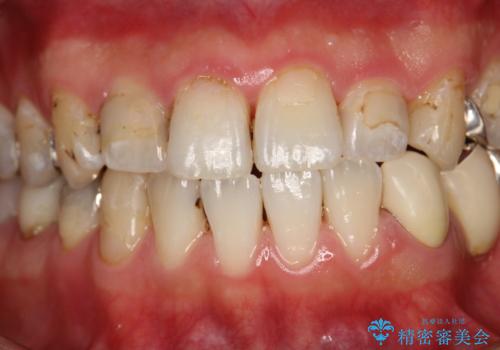

治療のスタート前に着色・ステインをPMTCできれいに除去

歯の表面に、茶色く色が残っている所がありますが、これは詰め物の変色の所と、虫歯になっている所です。以前に、CR(コンポジットレジン)による虫歯治療がされています。

CRは経年的劣化や、着色してしまうことがあります。PMTCでクリーニングを行うと、古いCRが目立つことがあるため、気になる際は詰め替えを行います。

茶色くなっている部分が、着色なのか、劣化なのか、虫歯によるものなのかは判別が難しいことがあります。そのため、定期的にPMTCを行うことで状態の確認が的確に行えます。

また、治療が開始される前などにも、全体的にクリーニングを行いご自身本来の歯の色、状態を精密に確認することが大切です。